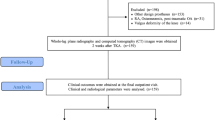

The study design was approved by the Ethics Review Committee (21010). All patients who participated provided written informed consent. Between 2019 and 2020, this retrospective case control study enrolled consecutive 53 patients who underwent TKA using an image-free handheld RA surgical system (Robot group) and between 2018 and 2019, this retrospective case control study enrolled consecutive 41 patients who performed TKA using a conventional manual surgical procedure (Manual group). The patients were not randomized and the same surgeon used the BCS prosthesis in both groups. The inclusion criteria were substantial pain, loss of function due to varus-type osteoarthritis of the knee and availability of complete data over 1 year of postoperative follow-up. Exclusion criteria included valgus-type osteoarthritis of the knee, rheumatoid arthritis, previous hip or knee arthroplasty surgery, severe bony defects requiring bone graft or augmentation, revision TKA, lumbar region problems, and active knee joint infection.